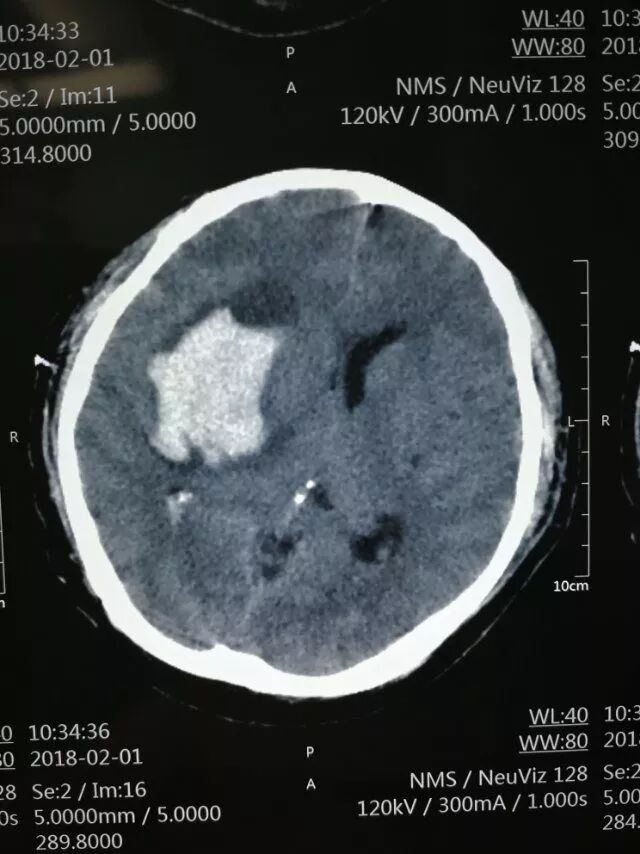

术后第一天复查